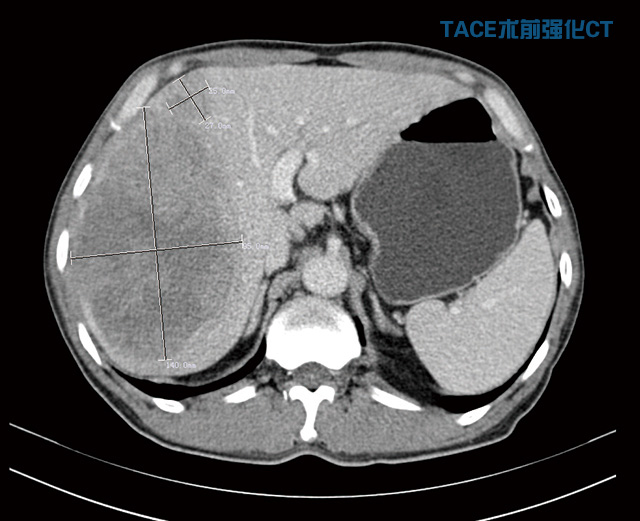

劉大爺是濰城區(qū)軍埠口鎮(zhèn)人,今年56歲。5個月前他右上腹部出現(xiàn)疼痛,在當(dāng)?shù)蒯t(yī)院檢查確診為晚期巨大肝癌,后來又去濰坊的大醫(yī)院復(fù)查,仍然是同樣的結(jié)果,醫(yī)生說已經(jīng)沒有治療的價值,建議他回家好好享受剩下的日子。就在他絕望的時候,同村的人向他介紹了濰坊市市立醫(yī)院,說這家醫(yī)院技術(shù)、服務(wù)都非常好,收費也便宜。他抱著試試看的心理住進我院普外科,經(jīng)過詳細檢查發(fā)現(xiàn),右肝巨大腫物約為14cm×12cm×9.5cm且伴仔瘤,肝硬化,左半肝變小,確診為原發(fā)性晚期巨大肝癌。

“這種情況不宜切除右半肝,因為左半肝體積小,余肝不能代償,切除后會導(dǎo)致肝功能衰竭,危及生命。必須先行介入治療,把供應(yīng)肝臟腫瘤的血管堵死, ‘餓死’癌細胞,使癌瘤縮小,左肝代償增大,待肝癌降期后再行手術(shù)治療,效果會比較好,也比較安全。”普外科首席專家李森主任分析說。期間劉大爺共經(jīng)過了2次介入治療,一個月前他來普外科復(fù)查時醫(yī)生告訴他腫瘤已明顯縮小,可以手術(shù),劉大爺心里一陣高興。